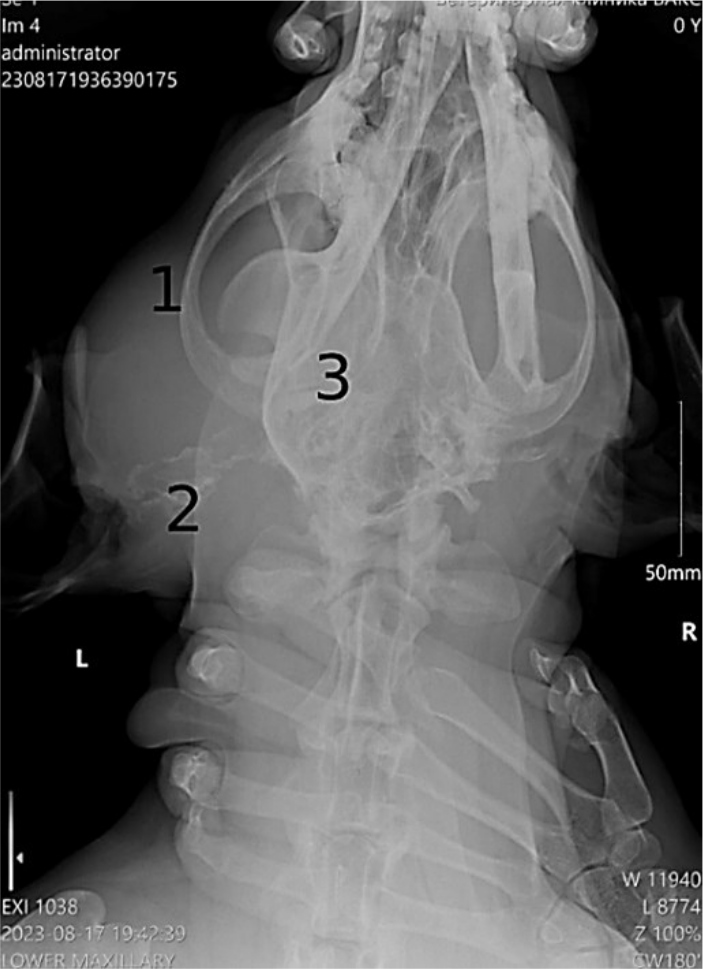

По результатам рентгенологического исследования: визуализация объемного мягкотканого новообразования средней рентген плотности в основании левой ушной раковины, не имеющих четких границ размером примерно 90×70 мм; Повышение периостальной реакции ростральной части левой скуловой дуги; минерализация слухового прохода на всем его протяжении; повышение рентген плотности левого барабанного пузыря, что характерно для склероза/кальциноза, не исключен средний отит (Рис. 3).

Рис. 3. Рентгенограмма, лабрадор, возраст 7 лет: 1 – мягкотканое новообразование; 2 – минерализация слухового прохода; 3 – повышение рентгенплотности левого барабанного пузыря